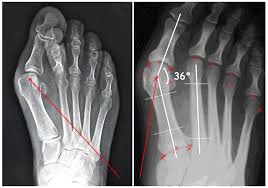

Chirurgia percutanea su alluce valgo,

Anche la chirurgia percutanea dell'alluce valgo consente la correzione in maniera mini-inva siva, cioè senza l'incisione cutanea classica, di questa frequente patologia, ma anche di altre deformità quali alluce rigido, dita a martello, metatarsalgie, dita sovraddotte, esostosi delle dita, etc., tramite piccoli fori di pochi millimetri e in anestesia locale, senza utilizzare nes-sun mezzo di sintesi interno o esterno.

Questa tecnica è indicata in casi di deformità fino al grado medio (circa il 70% dei casi); nel restante 30% dove si hanno importanti alterazioni strutturali del piede interessanti ossa, articolazioni, tendini e legamenti, trova la corretta indicazione una chirurgia mista percutanea-aperta o tutta a cielo aperto e il probabile utilizzo di mez-zi di sintesi permanenti o temporanei.

Controllo radiografico finale con bendaggio post-operatorio